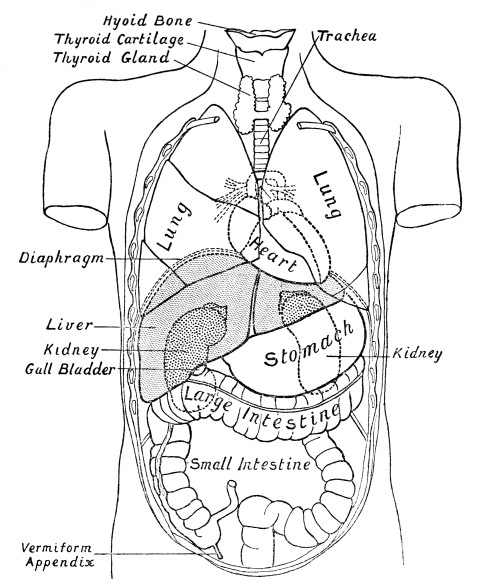

| 2. | The Organs of the Chest and Abdomen | xi |

Fig. 2.—Diagram

showing the Relative Positions of the Organs

of the Chest and Abdomen.

The ribs from the first to the tenth have been cut across in the lateral line. The eleventh and twelfth ribs do not reach sufficiently far forwards to be cut. With the exception of a short segment near its junction with the ascending colon, the small intestine has been removed. The trachea is seen to divide into bronchi beneath the arch of the aorta. The right lung has three, the left two lobes. The kidneys are situate behind all the other viscera. On their upper ends rest the two suprarenal capsules. The lower edge of the right lobe of the liver follows closely the line of the ribs and costal cartilages. Below the left lobe of the liver the stomach comes to the anterior abdominal wall. The transverse colon (large intestine) comes to the anterior wall below the stomach. Below the latter the wall is in contact chiefly with coils of small intestine. The vermiform appendix rests on the posterior wall. Spleen and pancreas are not shown in the diagram.